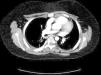

Se presenta un varón de 13 años con LESp y nefropatía lúpica de un año de evolución que presenta un TEP. Consulta por tos y disnea súbitas, acompañadas de dolor pleurítico y fiebre. Presenta taquicardia, taquipnea, tiraje universal, hipoventilación bibasal y saturación de oxígeno del 95%. Con la sospecha de TEP, ingresa en la UCIP y se determina el dímero-D, encontrándose elevado (1872 μg/l), confirmándose mediante TC helicoidal trombosis pulmonar en ambas arterias lobares inferiores (figs. 1 y 2). La radiografía muestra una elevación diafragmática derecha. Cardiológicamente, se evidencia pequeño derrame pericárdico y el característico patrón S1Q3T3 en el electrocardiograma. Se descarta trombosis venosa profunda. Se inicia precozmente tratamiento anticoagulante con heparina de bajo peso molecular, sustituyéndose a las 48 h por anticoagulante oral (dicumarínicos). Precisa ventilación mecánica no invasiva, mejorando a las 6 h la sintomatología.